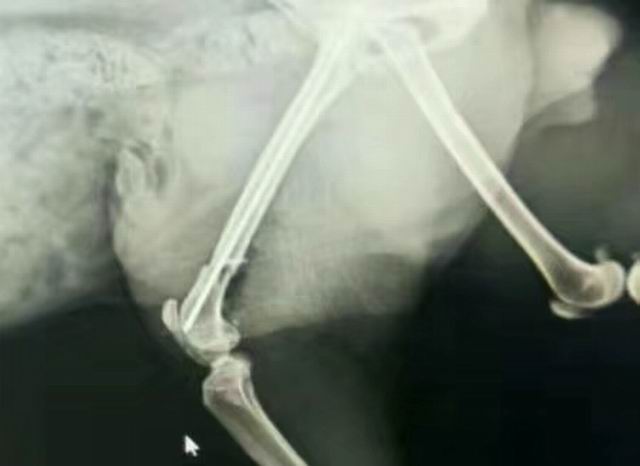

一例貓咪骨折/內(nèi)固定術

藍白,2歲,外固定失敗轉于我院,實施骨折內(nèi)固定,術前體檢+進口麻藥+手術順利(ok),住院護理中……急主人所急,想主人所想,致力于寵物健康,洛陽狗博仕寵物醫(yī)院